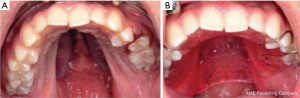

A fixed dental prosthesis is securely fixed to a natural tooth or teeth or dental implant(s) and cannot be removed by the patient. It can be used to restore teeth in partially edentulous arches or to restore clinical crown that is discolored, has abnormal or missing structure such as in amelogenesis imperfecta—a group of hereditary conditions that affect the structure and appearance of dental enamel (47) and ectodermal dysplasia patients respectively (Figure 5).

A less invasive composite resin direct restorations are usually preferred in adolescence to avoid excessive teeth preparation of younger patients (Figure 6) (49). Longevity of composite resin restorations is significantly lower when used in patients with enamel hypoplasia compared to those with hypomineralized or hypomatured amelogenesis imperfecta (50). Indirect restorations such as crowns are preferred over direct restorations based on scientific evidence in patients with amelogenesis imperfecta (49).